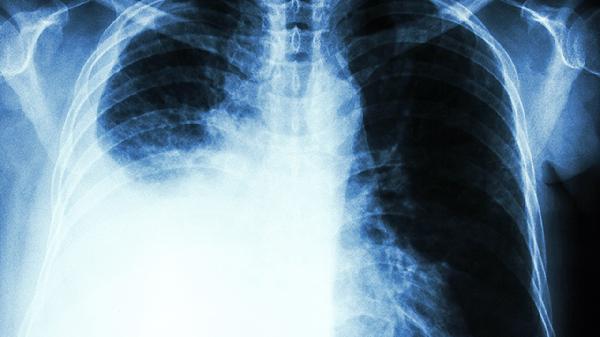

转移性肺结节的主要特征症状包括持续性干咳、胸痛、呼吸困难,并可能伴有全身症状如乏力或体重下降。出现这些症状时需尽早就医,通过影像检查和病理诊断明确病因,及时治疗。

初期,转移性肺结节可能无明显症状,尤其是体积较小时。但随着病程进展,会逐渐出现以下症状:

持续性干咳:是最常见的症状之一。干咳往往不伴随痰液,随病灶刺激或气道受影响加重,可发展为咳血。

胸痛:结节靠近胸膜或侵袭周围组织时,会引发胸部局部疼痛,特点为持续性或刺痛感。

呼吸困难:病灶增多或增大会压迫气管,影响肺的通气功能,导致患者逐渐出现气短或胸闷,特别是活动后症状更明显。